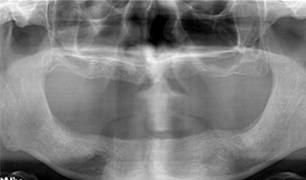

환자 성함 : 강** / 65세

2021.07.01 초진 사진